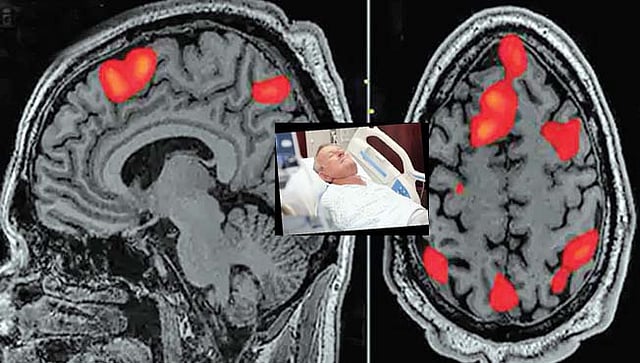

वैज्ञानिकांनी त्याला 'लास्ट रिकॉल' म्हणजेच 'आयुष्यातील शेवटची आठवण' असे नाव दिले आहे. अलीकडेच डॉक्टरांनी एका 87 वर्षांच्या व्यक्‍तीच्या मेंदूचे स्कॅनिंग केले. या व्यक्‍तीचा हॉस्पिटलमध्येच हार्टअ‍ॅटॅकने मृत्यू झाला. ज्यावेळी त्याच्या मेंदूचे स्कॅनिंग करण्यात आले त्यावेळी मृत्यूपूर्वी तीस सेकंद आधी त्याच्या मेंदूत तीव्र प्रकाश निर्माण झाला जो संबंधित व्यक्‍तीनेही पाहिला. मेंदूमध्ये रक्‍तप्रवाह थांबल्यानंतर काही मिनिटांनीही हे बदल घडत राहतात.

लुईसवील युनिव्हर्सिटीचे डॉ. अजमल जेमर यांनी सांगितले की मानवी मेंदू ही एक अतिशय गुंतागुंतीची गोष्ट आहे. या नव्या शोधामुळे न्यूरो सायन्सच्या क्षेत्रात बरीच मदत मिळू शकते. मेंदूच्या कार्याला समजून घेण्यासाठी तसेच रुग्णांवरील उपचारासाठी नव्या पद्धती शोधल्या जाऊ शकतात. सक्सेस युनिव्हर्सिटीचे प्रा. अनिल सेठ यांनी सांगितले की हा डेटा अतिशय अनोखा आहे. मृत्यूच्या काही सेकंद आधी मेंदूमध्ये काय घडत असते हे यामधून दिसून येते.

गेल्या दशकभरापासून अशा संशोधनासाठी प्रयत्न सुरू होते. संशोधक डॉ. जेमर यांनी सांगितले की मृत्यूपूर्वी मेंदूत तीवजए प्रकाश निर्माण होण्यामागे अल्फा आणि गॅमा लहरी कारणीभूत होतात. रक्‍तपुरवठा थांबल्यावर या लहरी काही सेकंद सक्रिय राहतात. याबाबत आणखी संशोधन गरजेचे आहे.